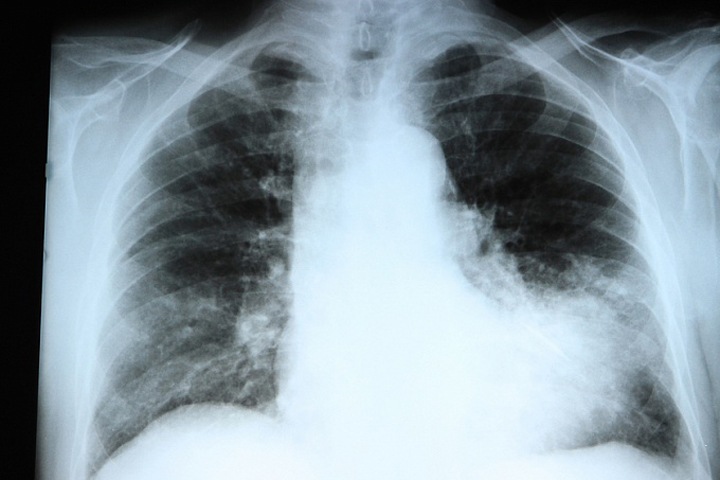

Однако в списке нет данных об уровне заболеваемости пневмонией, который за последние месяцы вырос в несколько раз. В декабре 2020 года (когда были опубликованы последние данные) было зафиксировано 5 059 случаев внебольничной пневмонии, что в 5,4 раза больше, чем в декабре предыдущего года, напоминает «СуперОмск».